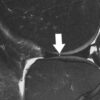

In releasing its new clinical practice guideline focused on acute isolated meniscal pathology, the American Academy of Orthopaedic Surgeons (AAOS) sought to help the medical community treat patients suspected of or diagnosed with an acute isolated meniscal tear. Acute isolated meniscal tears often occur from a traumatic injury with...